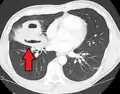

Computed tomography (CT) scan of chest showing bilateral pneumonia with abscesses, effusions, and caverns. 37-year-old male.

Lung abscesses are often on one side and single involving posterior segments of the upper lobes and the apical segments of the lower lobes as these areas are gravity dependent when lying down. Presence of air-fluid levels implies rupture into the bronchial tree or rarely growth of gas forming organism.